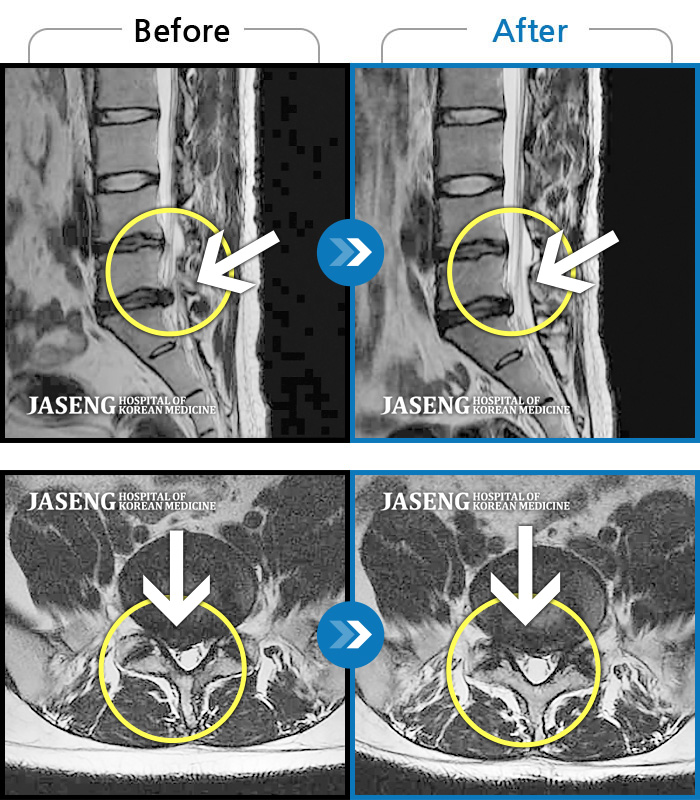

Before

After

환자에게 사전 동의를 받아 동일 조건에서 촬영되었습니다.

개인에 따라 치료 후 부작용이 발생할 수 있으니 의료진과 상담 후 치료를 진행하시기 바랍니다.

우측 허리통증 및 우측 엉치부터 발목외측까지 통증과 저림 증상

허리와 다리 통증으로 입원